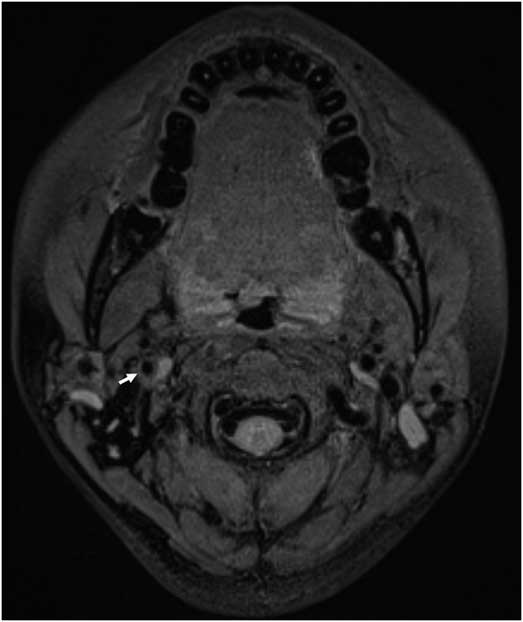

A 34-year-old healthy woman with transient left-side weakness and right-side blurred vision underwent radiologic evaluation. She had a history of minor head trauma during swimming 2 weeks before symptom onset. Initial fat-saturated T1-weighted DANTE-SPACE revealed bright mural hematoma signal (arrow) in the right internal carotid artery, suggestive of artery dissection. The excellent cancellation of blood-flow signal in the carotid lumen concomitant with consistent fat suppression (arrow heads) in the cervical region enabled clear depiction of CAD (Figure 1A). TFCA showed a tapered long segmental stenosis (arrows), which is a typical appearance of proximal carotid artery dissection (Figure 1B). The patient showed good clinical recovery and was subsequently discharged after 7 days. Follow-up MRI taken at 10 weeks after onset depicted resolution of the CAD (arrow) (Figure 2). In this case, non-invasive visualization of a dynamic change of CAD using DANTE-SPACE obviated the need for follow-up TFCA.

Figure 2 Follow-up T1-weighted DANTE-SPACE showed resolution of eccentric bright signal after 10 weeks.